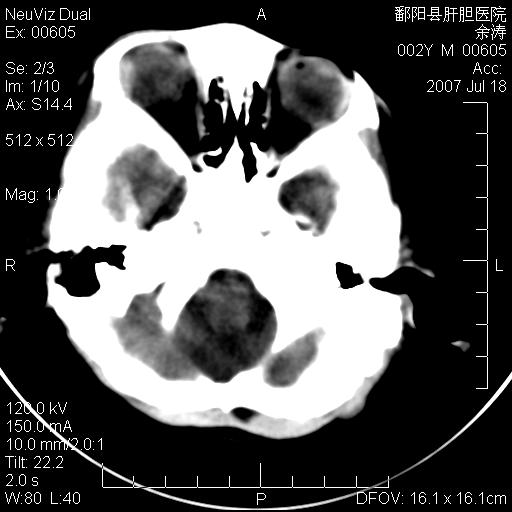

男性 2岁:平时智力障碍。外伤后行颅脑平扫。

考虑avm,建议增强扫描

脑裂畸形  血管畸形

考虑1.脑裂畸形。2.血管畸形。

2\\torch综合征.